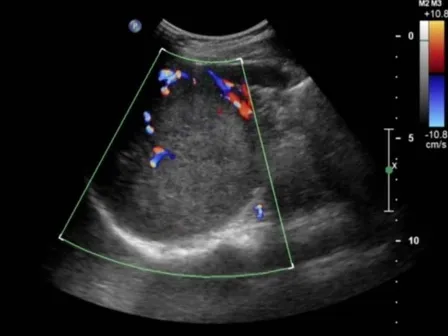

脾脏血管分布

彩色多普勒,正常脾脏,显示脾门处红色的脾动脉(SA)和蓝色的脾静脉(SV) 。